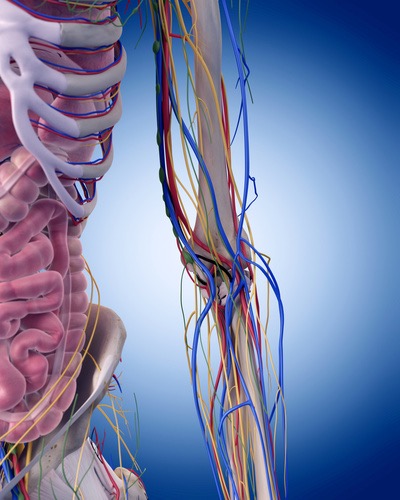

靭帯・血管・神経を特化したテクニック集をあなたにプレゼントすることにしました。

”痛みを完全に治すことができない”ということに悩んでいます。ですが、”完全に痛みを消失する”治すために必要なのは”筋膜以外の原因”を治療する知識とテクニックを学ぶことです。なので、今回は”靭帯・血管・神経”に特化した商品をあなたに無料でプレゼントすることを決めました。

- 今まで筋肉・筋膜を単体で見ていた状態から、血管・靭帯・神経を治療することで今まで改善できなかった患者さんを救うことができます。

「血管」「靭帯」「神経」と筋膜のつながりのデータを公開

このセッションでは、血管・靭帯・神経をあなたの臨床に取り入れやすくするために筋膜との関係性を明らかにします。例えば腕神経叢は斜角筋と繋がりがありますし、坐骨神経は梨状筋との繋がりがあります。この知識さえあれば、どのタイミングで血管や神経を見ればいいのかがわかり。明日からの臨床ですぐに結果を出すことができるでしょう。